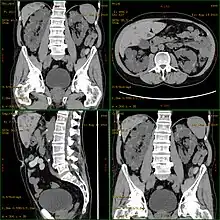

| Severely affected polycystic kidneys removed at time of transplantation | |

| Diagnostic method | MRI, CT scan, Ultrasound[1] |

Diagnosis may be suspected from one, some, or all of the following: new onset flank pain or red urine; a positive family history; palpation of enlarged kidneys on physical exam; an incidental finding on abdominal sonogram; or an incidental finding of abnormal kidney function on routine lab work (BUN, serum creatinine, or eGFR). Definitive diagnosis is made by abdominal CT exam.

Polycystic kidney disease can be ascertained via a CT scan of abdomen, as well as an MRI and ultrasound of the same area.[23] A physical exam/test can reveal enlarged liver, heart murmurs and elevated blood pressure.[1]